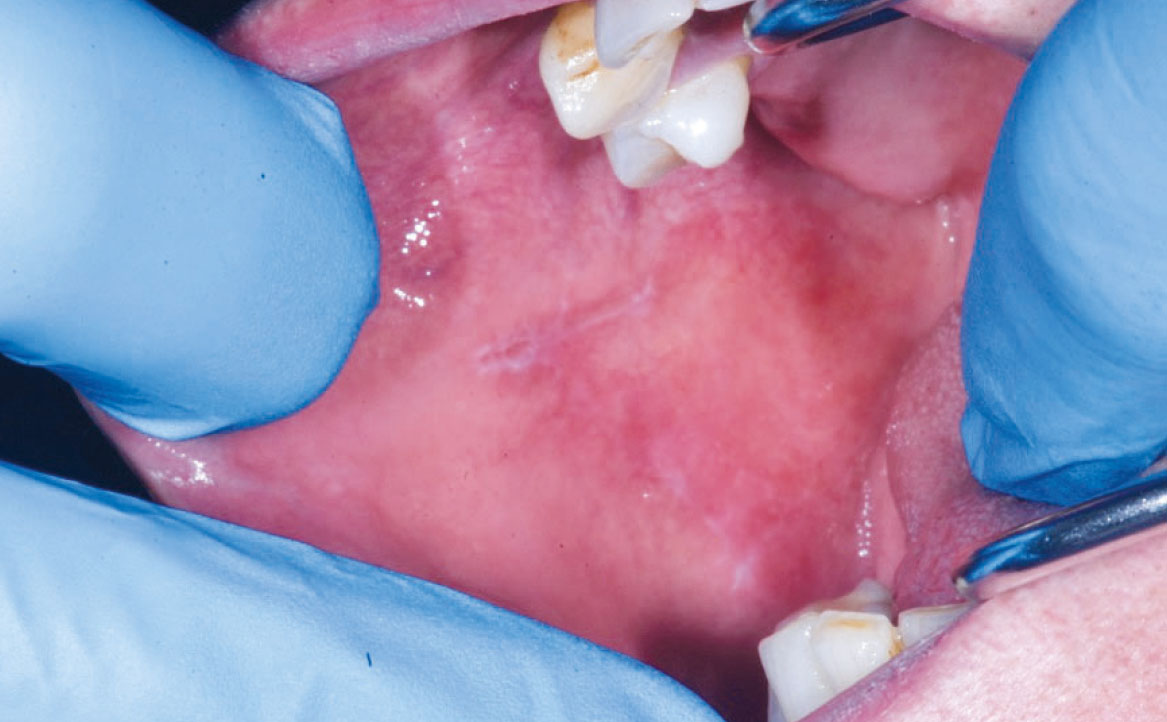

Le reazioni o lesioni lichenoidi orali presentano una similitudine clinica con le lesioni da lichen planus orale, sebbene si distinguano per una marcata componente eritematosa/erosiva e una distribuzione unilaterale delle lesioni, in particolare sulla mucosa geniena e sul dorso e margine laterale della lingua. Inoltre, a differenza del lichen planus, queste reazioni consentono di individuare la causa scatenante e vengono classificate in base all’agente causale coinvolto, che può essere il contatto diretto con materiali di restauro dentale o lesioni farmaco-correlate (17).

Più di 50 diversi farmaci sono stati associati a questo tipo di lesioni, tra cui i più comuni sono gli antipertensivi, compresi i β-bloccanti, gli ACE inibitori e i diuretici. In aggiunta, anche farmaci antidiabetici come le sulfaniluree (tolbutamide e glipizide), antimicotici come il ketoconazolo, anticonvulsivanti come la carbamazepina, farmaci immunomodulatori come i sali d’oro e la penicillamina, la sulfasalazina e l’allopurinolo sono stati segnalati come agenti responsabili delle LR (fig. 3) Questi farmaci sono spesso utilizzati in combinazione, suggerendo un possibile effetto sinergico (19).